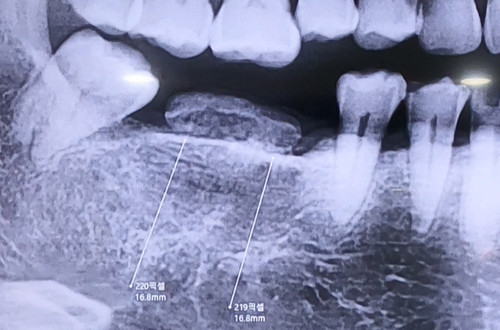

엑스레이를 찍어 보니, 이를 뺀 지 오래 되어 잇몸이 아물어

잇몸뼈는 단단하고 상태가 좋았는데, 임플란트를 하려는 부위

위쪽으로 튀어나온 무언가가 보여 더 정밀하게 검사하였습니다.

환자분은 치아 주위를 둘러싼 뼈들이 볼록하게 튀어나온 형태인

하악골융기가 일반적인 경우보다 컸고 치아 바깥쪽으로도

많이 튀어나와 있어서 식립 위치를 정확하게 잡아야 했습니다.

때문에 CT촬영을 통해 정확한 잇몸뼈 모양과 구조를 파악하고

임플란트를 진행한, 조금 특수한 케이스였습니다.